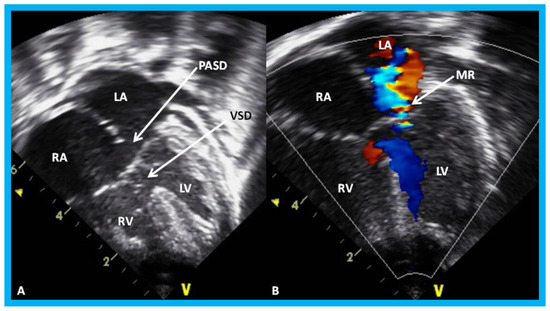

Usefulness of echocardiogram in evaluation of infant of a diabetic mother (IDM) (Figure 25, Figure 26 and Figure 27), PDA in premature babies (will be reviewed in the next section), side of the aortic arch in tracheo-esophageal fistula babies (Figure 28), heart defects in Down syndrome (Figure 29), and cardiomegaly (Figure 30 and Figure 31) were elucidated.

Figure 29. Apical four-chamber view of the heart in baby with Down syndrome demonstrating atrioventricular septal defect in 2D (A) and color-Doppler imaging (B): Ostium primum atrial septal defect (PASD) and ventricular septal defect (VSD) are shown (arrows) in (A) and mitral regurgitation (MR) in (B) (arrow). LA, left atrium; LV, left ventricle; RA, right atrium; RV, right ventricle.